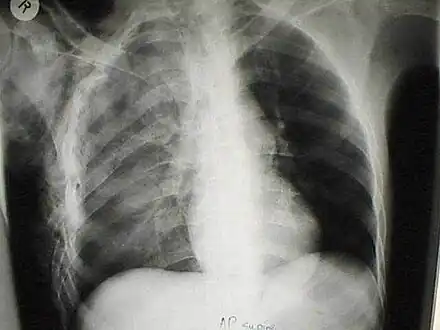

A chest X-ray of a right sided pulmonary contusion associated with flail chest and subcutaneous emphysema